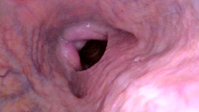

In the animal with an ocular tumor and infra-auricular metastasis (Figure 1), we noticed the collapse of the palatopharyngeal arch, epiglottic entrapment, vascular increase of the left pharyngeal wall (corresponding side of the tumor), flaccidity of the rostral pharyngeal constrictor muscle, palatal flaccidity, where all the findings are consistent with the innervation corresponding to pairs IX, X and XII, where we cannot fail to mention the muscles that tense and elevate the soft palate, which in Figures 4 and 5a,b) shows its complete collapse.

Figures 4, 5(a, b), 6 We notice complete epiglottic entrapment, collapse of the palatal arch, vascular enlargement of the right pharyngeal wall -side of the tumor.

Figure 5b Eiglottic entrapment.

The complex innervation of the oropharyngeal region has its main origin in pairs IX, m.elevator veli palatini, m.constrictor pharyngeus rostral, m.pterigo pharyngeus and m.palatopharyngeus8–12 which may be of great importance in the equine species and still very little studied as the findings in the bovine species are very compatible with respiratory problems in horses with low performance, such as epiglottic entrapment and palatal collapse. In cattle with epiglottic entrapment (Figure 5a and 5b) we can say that the palatal tensor no longer maintains the aforementioned functional structure, but in cattle of little clinical importance or still little known, but in equine athletes of vital importance; the IX pair arises outside the central nervous system in the posterior region of the parotid gland, which explains the choice of cattle with tumors in this region, as well as the VII, VIII, X, XI and XII pairs, as well as all their respective branches that from what this experiment showed, based on the endoscopies performed, the lesions mainly in the muscles that tension the soft palate, dorsal palatal region, even with unilateral tumoration have a response, in the oropharyngeal muscles examined, bilaterally, but more accentuated on the corresponding side of the presence of the tumor (Figure 7).

Comparatively, we can make some parallels between the images of equine epiglottic entrapment (Figure 7–10), collapse of the palatal arch (Figure 7), low muscle tension of the soft palate (Figure 10), unilateral edema of the cuneiform recess (Figure 7) , in cattle with findings in horses with low performance with etiology in the upper portion of the airways or oropharynx, where the comparative study proved to be an interesting model for the study of the anatomical structures involved in the "sagging" of the soft tissues of the upper airways in horses and apparently of not well understood importance in cattle, where these processes reduce airflow in the respiratory tract. In horses, we can explain that this loss of palatal and oropharyngeal tone, in general, the regional lymph nodes are in contact with the pharyngeal branches of the glossopharyngeal and vagus nerves and retropharyngeal lymphadenopathy (increased volume and infra-auricular tumoration, Figure 1,2) could result in compression and irritation,11 a very important fact for equine athletes but apparently not so important in cattle, as they, with the presence of large tumors, did not show signs of dyspnea, respiratory discomfort or even any form of postural compensation to improve breathing.

Figure 10 Bovine soft palatal collapse. These images show the similarity of problems in two species - cattle and horses.